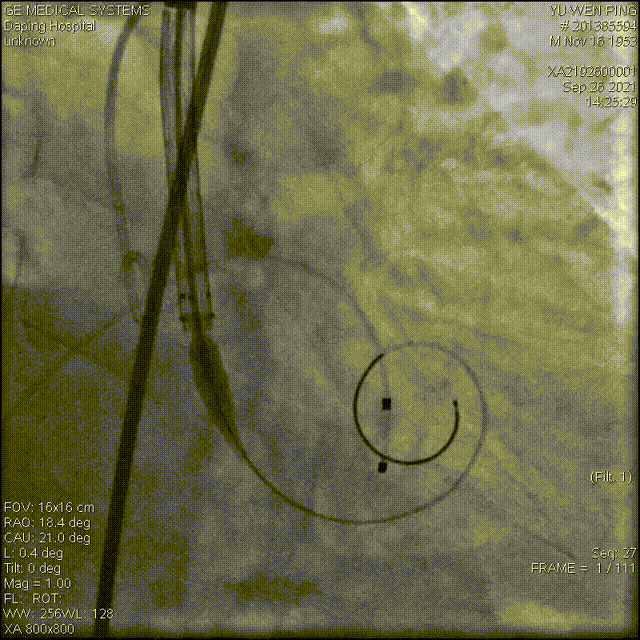

术中影像

以 Seldinger法穿刺右桡动脉,使用Pig造影导管行主动脉根部造影

20mm球囊预扩,有腰无漏

造影确定释放位置

释放成功,但存在中度瓣周漏,经20mm球囊后扩,造影见微量瓣周漏,较前明显好转